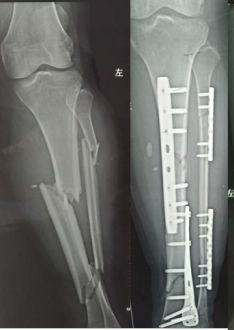

两处腓骨钢板多余(因为下胫腓骨联合没有损伤,特别注意不要犯这种错误)(髓内钉加阻挡钉首选,其次内侧长钢板,如果没有钢板用外固定架也可以)

胫骨远端简单骨折选用钢板固定没有实现坚强固定,钢板承受应力,孔处应力集中断裂

更换长钢板后愈合

下一例:是胫骨骨折局部钢丝螺钉内固定太多干扰骨愈合,骨不连接钢板迟早断裂。

开放骨折,软组织损伤严重,骨不连接导致钢板断裂。应当在伤口愈合后及时干预植骨